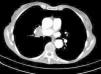

Mujer de 68 años que ingresa con cuadro progresivo de cefalea holocraneal, deterioro cognitivo de rápida evolución y síndrome constitucional. Una tomografía computarizada torácica (fig. 1) evidenció una masa en zona parahiliar del pulmón derecho. Como parte del estudio se realiza una RM cerebral que mostró niveles rectos de interfase líquido-sólido en las astas occipitales (fig. 2), con restricción del movimiento del agua libre en secuencia ADC y moderadamente brillante en secuencias de difusión altamente indicativo de corresponder a depósitos celulares.

Una RM posterior evidenció un discreto aumento de los depósitos ventriculares.